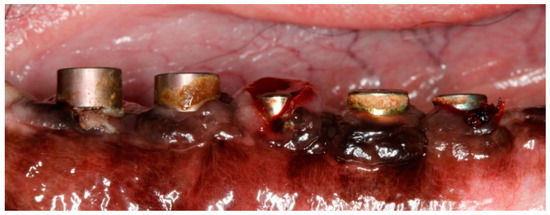

Implants were exposed 3 months post-implantation and their healing abutments were connected (Figure 3). The flaps were adjusted around the titanium abutments with interrupted sutures. No oral hygiene regimen was administrated during this period, so that the peri-implant inflammation could initiate spontaneously. Five months post-implantation (two months post implant exposure), to accelerate the progression of the initial lesions, cotton ligatures were placed according to the method described by Lindhe et al. [23] in a submarginal position around the neck of implant No. 1, two months later at implant No. 3 and, after another two months, at implant No. 5 (Figure 4). Two intermediate implants (No. 2 and No. 4) were left without ligatures. The ligatures were not replaced or removed during this experiment. The animal was then fed a soft diet to induce plaque accumulation and to provoke peri-implant inflammation and the loss of bone.

Figure 4. Post-operative image at 9-month post-implantation. Note the ligatures placed in alternating implants 1, 3 and 5, and the subsequent local inflammation.

In the above-mentioned study models, ligatures of cotton, silk or metal [51] were placed around properly integrated implants and forced into a submarginal position. Ligature placement compromised the mucosal attachment to the implant and promoted the buildup of plaque [14,23]. It was noted that inflammatory lesions rapidly formed, and bone loss occurred [13,23,52,53]. Unlike most of the aforementioned studies, where the ligatures were removed after the desired amount of tissue destruction was achieved, in our study ligatures were kept in contact with the peri-implant tissue during the whole experimental period, similar only to a more recent study design [42]. In our model, five months post-implantation (two months post implant exposure), to accelerate the progression of the initial lesions, cotton ligatures were placed in a submarginal position around the neck of implant No.1, two months later at implant No.3 and, after another two months, at implant No.5 (Figure 4). Two intermediate implants (No.2 and No.4) were left without ligatures, to compare the tissue breakdown between ligature-induced and spontaneous peri-implantitis in alternatively ligated implants. Additionally, the ligatures were placed at different timepoints, so that the progression in time of the lesions could be observed. After ligature-induced plaque accumulated on the implant abutment, the following loss of epithelial sealing [23] allowed the plaque front to continue to migrate apically undisturbed. However, generating „true” early peri-implant defects without the mechanical trauma of ligature placement was hypothesized in 2014 [25] and was demonstrated very recently [26]. To complement this approach, which separates the onset and progression of peri-implantitis on implants with different levels of plaque control, the present study addressed the influence of subsequently ligatured implants on adjacent non-ligatured implants in the same hemimandible in an orally compromised canine model that facilitated naturally occurring mucositis and subsequent peri-implantitis due to heavy, long-time, unrestricted dental plaque accumulation [26].